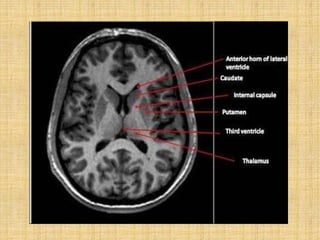

It is a C shaped mass of grey matter

Derived from telencephalon.

Consists of large head, body and

thin tail.

Relations

It is intimately related to the lateral

ventricle.

•Head - bulges into anterior horn of

the ventricle and forms its floor. It is

continuous with the putamen.

•The body lies in the floor of the

central part of the ventricle

•Tail in the roof of the inferior horn

of the ventricle.

The anterior part of the head is fused with the lentiform

nucleus inferiorly. This region is called fundus striati.

Fundus striati is continuous inferiorly with the anterior

perforated substance.

The tail lies in close relation to the amygdaloid

complex.

The body is

related mediallytothe

thalamus

and laterally to the

which

internal capsule

seperates it

from

the

lentiform nucleus.

Lentiform nucleus

Appears triangular in

the coronal section with

its tip directed medially.

Divided by a thin lamina

of white matter known

as external medullary

lamina into

 Lateral part- putamen

 Medial part- globus

pallidus